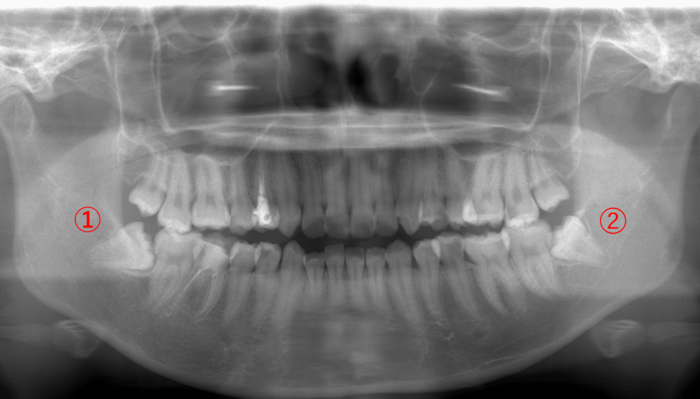

| 年齢・性別 | 27歳・男性 |

|---|---|

| 主訴 | 親知らずに食べ物が挟まる。 |

| 歯ブラシ | 毎日歯を磨いている。汚れが残っていて、うまく磨けていない。 |

親知らずの周りには、汚れがびっしりと付着しています。

画像➁の親知らずは横向きに生えているため、食べる度に手前⑤の歯との隙間に食べ物が挟まり、虫歯になっています。

このような場合は、早めに親知らずを抜いて手前⑤の歯の虫歯を治療した方が良く、また②の親知らずを抜くと上の④の親知らずが下がってくるため、一緒に抜いた方が良いです。

そして反対側①の親知らずは、顔を出しているので、歯ブラシが上手くできないのであれば抜いた方が良いこと、③に関しては、顔を出してない親知らずのため、無理して抜かなくても良いと説明しました。

食べ物が挟まる形態の親知らずは、隣の歯に影響を及ぼすため、抜いた方が良いことが多いです。